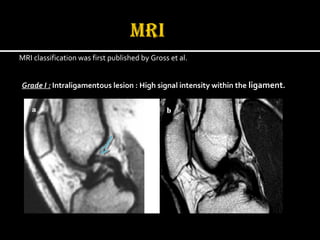

MRI classification was first published by Gross et al.

Grade I : Intraligamentous lesion : High signal intensity within the ligament.

Grade II : Partial lesion: High intensity signal on the dorsal edge of the ligament.)

Grade III: Partial lesion : High signal intensity on the ventral edge of the ligament.

Grade IV: Complete lesion : No remaining fibres are detected.